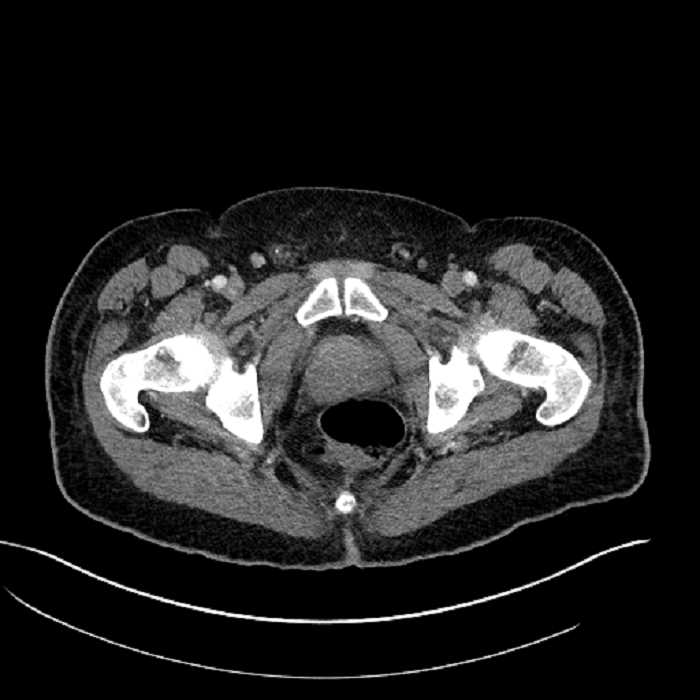

• High grade stenosis of the left common iliac artery, with the left internal and external iliac arteries remaining patent

• Ankylosis of both sacroiliac joints

High grade stenosis of the left common iliac artery. The left external and internal iliac arteries are patent.

Hepatic abscess showing the double target sign with low density internally surrounded by a thin inner enhancing rim (red arrow) and ill-defined outer low density rim (yellow arrow). Blue arrow indicates an internal septation. Red arrows: additional smaller subcapsular abscesses. Red arrow: focal contained perforation associated with diverticulitis.